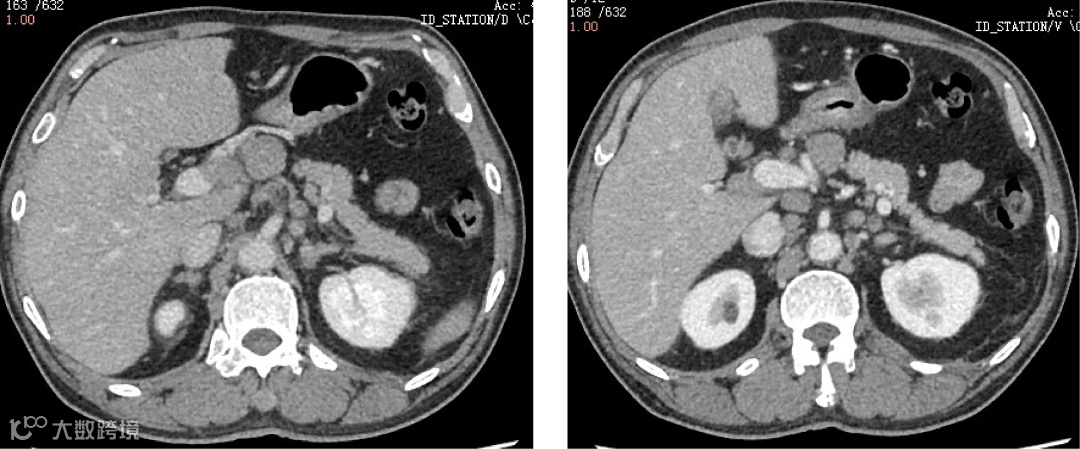

双侧内乳区、膈上、右侧膈肌脚区、肝门区、肝胃间隙、脾门区、腹膜后多发淋巴结,肝脾肿大,代谢增高;脊柱多个椎体及部分附件、双侧肱骨、双侧肩胛骨、双侧锁骨、双侧多根肋骨、胸骨、骨盆诸组成骨、双侧股骨上段多发代谢异常增高灶。